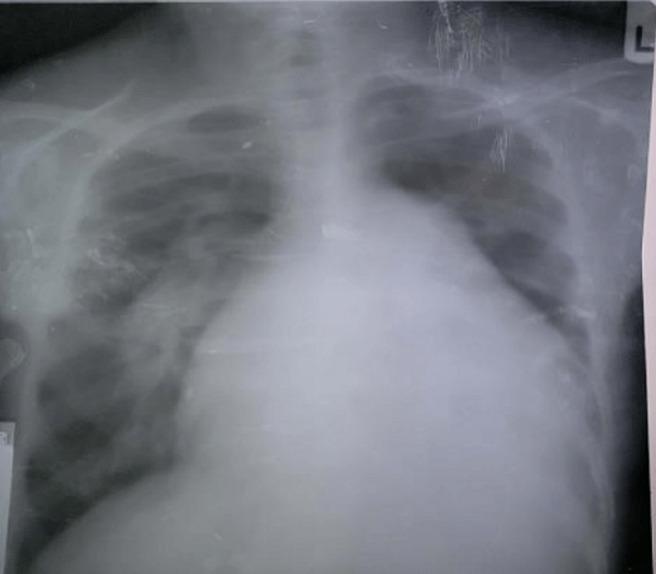

Lutembacher syndrome (LS) is a rare syndrome comprising a combination of atrial septal defect (ASD) and mitral stenosis. We present the case of a 28-year-old man, who presented with progressively worsening dyspnea of 2 months associated with orthopnea, paroxysmal nocturnal dyspnea, bilateral leg swelling and productive cough. Chest X-ray revealed plethoric lung fields with prominent pulmonary conus and cardiomegaly. Transthoracic echocardiography revealed a large ostium secundum ASD with left to right shunt, mild mitral stenosis, severe mitral and tricuspid regurgitations and pulmonary hypertension. A diagnosis of Lutembacher syndrome in heart failure with pulmonary hypertension was made. The patient was managed conservatively, but declined surgery primarily because of financial reasons. This rare case of LS presenting with heart failure and complicated by pulmonary hypertension is the first reported case in our centre and our region. The patient's inability to afford the cost of definitive care posed a significant problem in his management.

卢特巴赫综合征(LS)是一种罕见的综合征,包括房间隔缺损(ASD)和二尖瓣狭窄。我们报告了一例 28 岁男性病例,该患者出现进行性恶化的呼吸困难,病程为 2 个月,伴有端坐呼吸、阵发性夜间呼吸困难、双侧腿部肿胀和咳嗽有痰。胸部 X 线显示肺部过度充气,肺动脉圆锥突出,心脏增大。经胸超声心动图显示继发孔 ASD 大,左向右分流,二尖瓣轻度狭窄,二尖瓣和三尖瓣重度反流和肺动脉高压。诊断为心力衰竭合并肺动脉高压的卢特巴赫综合征。患者接受了保守治疗,但主要由于经济原因拒绝手术。这例罕见的 LS 合并心力衰竭和肺动脉高压的病例是我们中心和我们地区首例报告。患者无力承担确定性治疗的费用,这在他的管理中构成了一个重大问题。